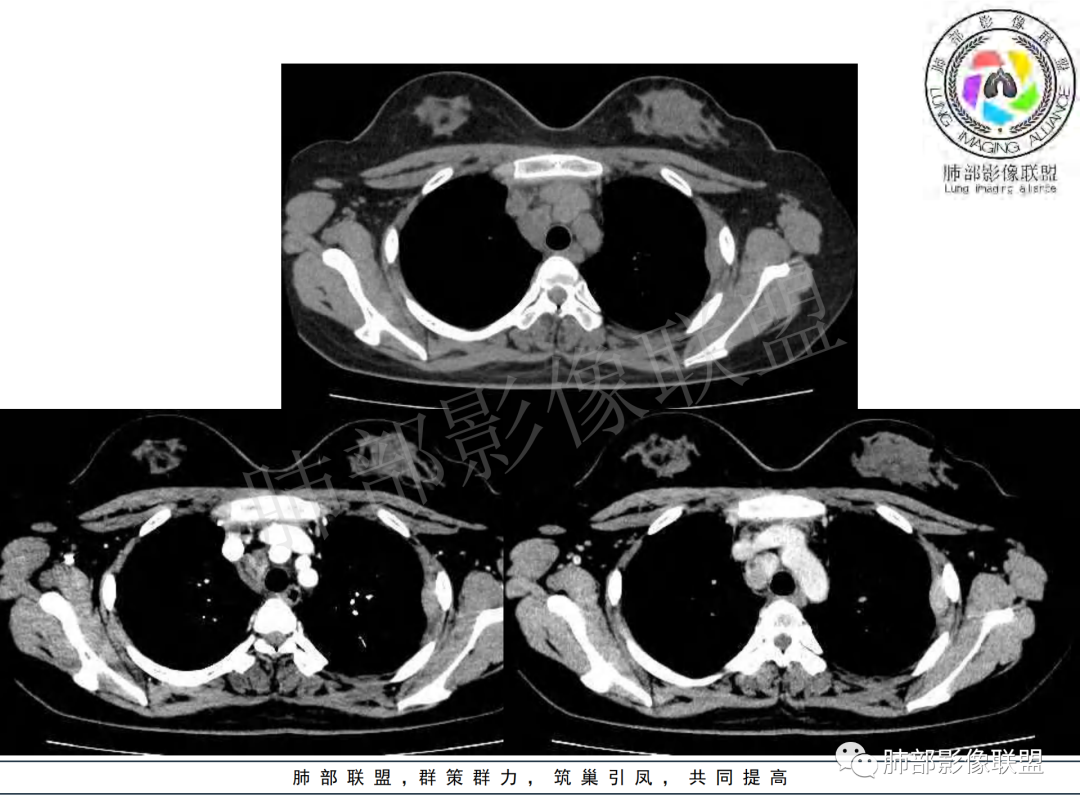

纵隔多组及右侧肺门多发肿大淋巴结,部分融合,不均匀强化,内见斑片状坏死区及环状强化,后者坏死边界尚清晰,肺门区肿大淋巴结与肺组织边界不清,年轻女性,8个月病史,发热首发症状,考虑淋巴结核并向肺内侵及(破溃?),鉴别淋巴瘤

女,20,病程长达8月,发热、胸痛、右侧胸腔积液病史。胸部CT:右肺门旁不规则肿块影,右中间支气管腔内结节,纵隔多发淋巴结肿大;强化不均匀,灶性坏死灶,环形强化;右侧少量胸腔积液并局部肉芽肿样突起。年轻女性,长病程,多部位,考虑慢性炎症,结核?鉴别肿瘤。

女性,20岁。高热、畏寒。右肺上叶近肺门区不规则肿块,周围斑点、片小结节影伴肿大淋巴结,肿块包绕并突入右主支气管腔内,增强后肿块不均匀强化,淋巴结环形强化中心低密度,考虑结核。

本例患者,年轻女性,慢性病程,多次抗感染治疗效果不佳,实验室检查示白细胞及中性粒细胞不高,不支持普通细菌感染,虽然肺泡灌洗液X-Pert检测阴性,结合患者胸部CT结核感染亦不能排除,胸部CT主要表现为右侧肺门及纵隔淋巴结肿大,仔细观察不难发现右中间支气管内新生物凸向管腔内,增强扫描,右肺门(10R)及纵隔淋巴结(2R,4R)明显不均匀强化,内部呈不规则低密度无强化区,被周边高强化区包绕(环形强化)的特点,首先应当想到纵隔淋巴结结核诊断。淋巴结分布亦不符合肺部恶性肿瘤迁徙途径。